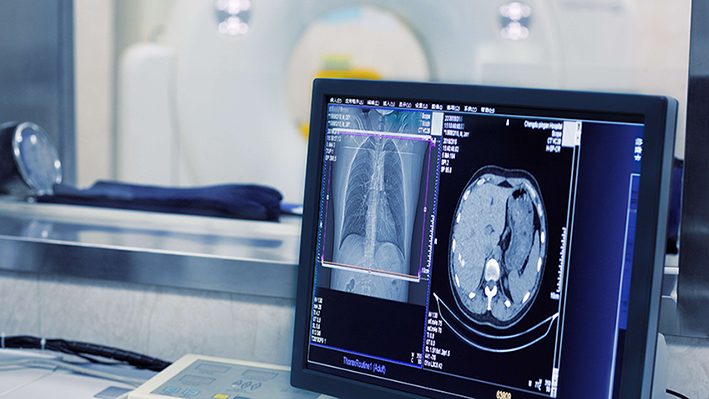

AIMEDIC utilizes advanced machine learning and deep learning algorithms to analyze mammography images with high precision. By detecting hidden lesions and abnormalities in breast tissue, the platform significantly aids radiologists in early and accurate diagnosis of breast diseases.

In addition to processing medical imaging data from various devices, the platform generates structured reports through its integrated reporting module, enabling radiologists to provide more accurate clinical assessments.

Key advantages of AIMEDIC include enhanced diagnostic accuracy, reduced error rates, faster image analysis, and decreased radiologist workload.